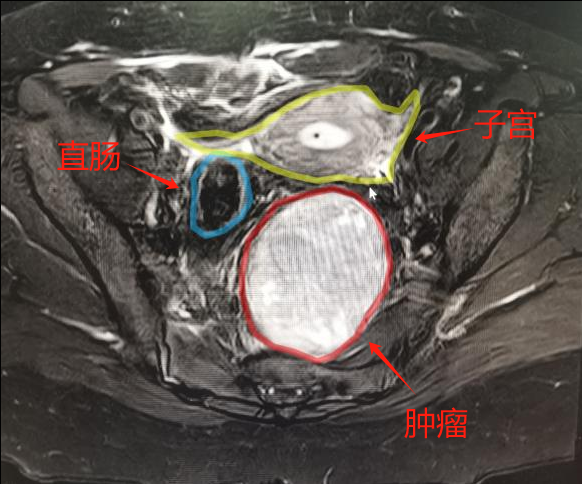

近日,我院普外三科完成一例腹腔镜辅助下困难盆腔肿瘤根治性切除术,此病例是我院盆腔疑难肿瘤诊疗中心成立后首例盆腔困难肿瘤手术。 患者在当地医院手术中发现肿瘤,...